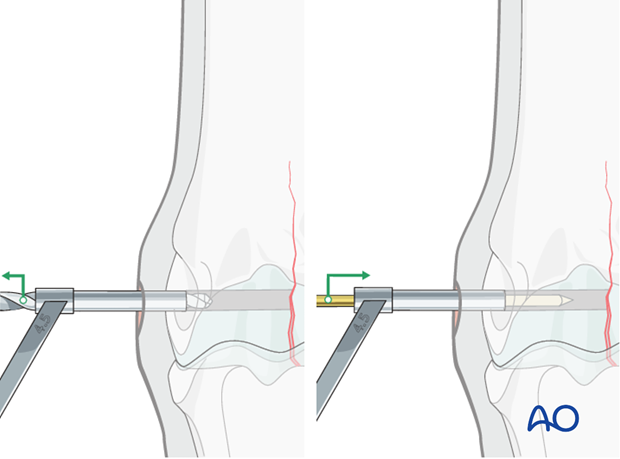

The 4.5 mm drill guide is subsequently placed over the 2.5 mm pin (A). The pin is removed (B) ...

... and the 4.5 mm tap inserted through the guide (C).

The hole is tapped routinely, keeping the very dense bone in mind. It is critical to tap completely through the far cortex (red circle). The bone is so dense that even a single millimeter of untapped bone may prevent complete insertion and tightening of the screw.

A long tap is strongly preferred to avoid impinging the end of the drill on the edge of the drill guide (yellow circle). This could result in stripping the threads in the hole or breaking the tap.